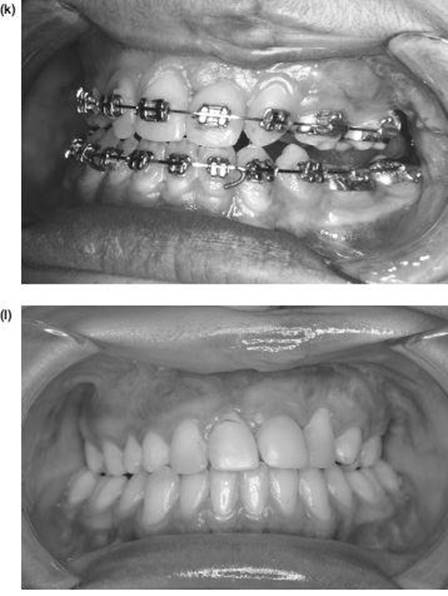

The Inverted L Osteotomy

Indications

This operation is valuable when there is a need to increase both the ramus height and body length at the same time, especially when the sagittal split osteotomy is not possible. Such cases are usually gross congenital mandibular hypoplasia or, occasionally, acquired hypoplasia following condylar fractures or when previous surgery has disturbed the bony anatomy. The operation differs in concept from the sagittal split procedure in that a bone graft is inserted to make up the deficiency.

Technique

1. The surgical approach is exactly the same as for the extraoral subsigmoid osteotomy (steps 1-6 and see Figure 9.4) except that the bone cut is made from the anterior border of the ascending ramus, passing distally, to behind the estimated position of the lingula then downwards to the lower border anterior to the angle, i.e. to the antegonial notch (Figure 9.7a).

2. With bilateral deformities the approach is repeated on the opposite side.

3. The mandible is then temporarily fixed into occlusion. Where the maxilla is normal this presents no problems. However, if there is a deformity of the maxilla this must be corrected before the inverted L and fixed with bone plates.

Mobilising the small mandible into the desired anterior position can be difficult and is facilitated by drilling a hole bilaterally in the lower border of the mandible just anterior to the osteotomy cut and passing a 0.5 mm traction wire to be attached to heavy forceps. When anterior traction is applied, explore the deep tissues medial to the mandible with a finger to find any restraining bands of periosteum, muscle or ligament. These must be vigorously divided with the finger to ensure stability.

4. With the proximal condylar fragment confirmed to be in the fossa, the gap created can be measured, and a template formed with sterile paper or card.

Figure 9.7 (a), (b)

5. An interpositional graft is now obtained. The ideal source is cortico-cancellous bone from the iliac crest. A solid cancellous graft can be used but the incorporation of one cortex provides reassuring stability. Some surgeons use split rib for the gap. Two miniature bone plates provide excellent rigidity and form (Figure 9.7b).

6. A vacuum drain is inserted and the wound is closed in layers.

7. The intermaxillary fixation is released and the pack removed.

Note: Any mandible which requires lengthening with an inverted L osteotomy also requires an augmentation genioplasty.